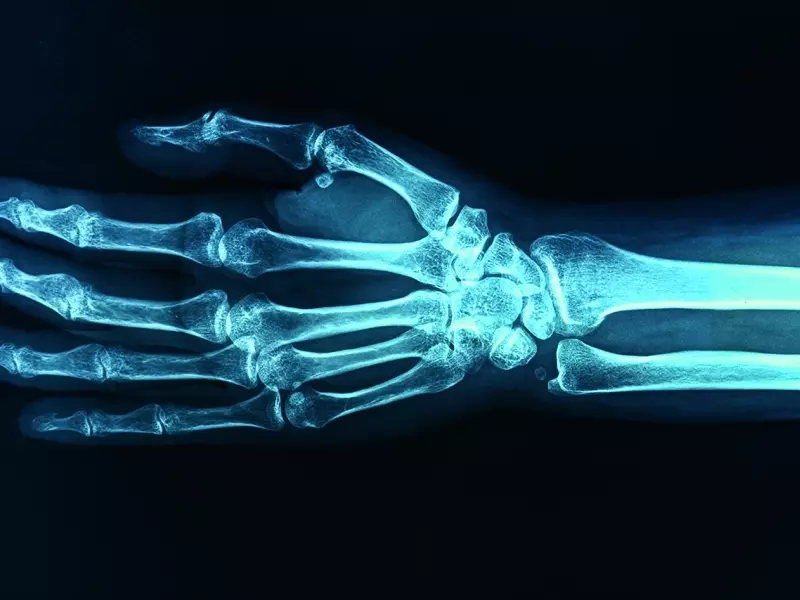

Diagnostyka zespołu cieśni kanału nadgarstka dla potrzeb fizjoterapii

Zespół cieśni nadgarstka to jedna z najczęstszych neuropatii obwodowych w obrębie kończyny górnej. Dotyczy 3% populacji w średnim i starszym wieku, przeważnie występuje u kobiet, osób z nadwagą lub otyłością oraz wykonujących pracę umysłową, głównie przed komputerem. Charakteryzuje się bólem, parestezjami występującymi w nocy w obrębie I, II i III palca, osłabieniem siły mięśniowej lub nawet zanikiem kłębu kciuka. W celu wykrycia i potwierdzenia zespołu cieśni kanału nadgarstka stosuje się dokładną diagnostykę, począwszy od wywiadu, testów prowokacyjnych, oceny siły mięśniowej po bardziej

obiektywne badania obrazowe. Celem pracy jest przedstawienie metod diagnostyki neuropatii obwodowej kończyny górnej, jaką jest zespół cieśni kanału nadgarstka.

Zespół cieśni nadgarstka jest neuropatią uciskową i dotyczy nerwu pośrodkowego. Dotyka głównie kobiet po 50. roku życia wykonujących prace biurowe. Zwykle odnosi się do ręki dominującej, choć w 60% ma przebieg obustronny [1]. Neuropatia ta jest spowodowana zwiększonym ciśnieniem w kanale nadgarstka wynoszącym ponad 30 mm Hg. Wraz ze wzrostem ciśnienia dochodzi do zmniejszenia przepływu krwi w naczyniach włosowatych nerwu pośrodkowego. Skutkiem tego może być zaburzenie jego prawidłowego odżywienia, wystąpienie dolegliwości bólowych lub parestezji [2]. W pierwszym etapie, gdy objawy nie są stałe i zbyt uciążliwe, pacjenci nie zgłaszają się do specjalisty w celu dokładniejszej diagnozy. Przy dłuższym, przetrwałym, utrzymującym się zwiększonym ciśnieniu w obrębie kanału nadgarstka dochodzi do zmian morfologicznych w strukturze nerwu, a dokładniej jego demielinizacji lub zwyrodnienia aksonalnego [3]. Gdy ciśnienie przekroczy 30 mm Hg u pacjentów pojawiają się łagodne objawy. Po przekroczeniu wartości ciśnienia 40–50 mm Hg w kanale nadgarstka dolegliwości stają się bardzo dokuczliwe i są oceniane przez pacjentów jako mocne lub silne [4].